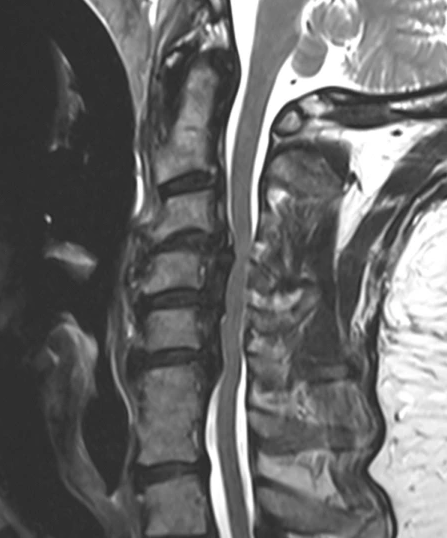

OPLL은 척추관을 따라 이어지는 후방 종인대가 두꺼워지고 골화되는 질환입니다. 이러한 골화 과정은 경추(목) 부위의 척수와 신경 뿌리를 압박하여 통증, 뻣뻣함, 신경학적 문제를 비롯한 다양한 증상을 유발할 수 있습니다.

OPLL을 진단하기 위해 의료 서비스 제공자는 일반적으로 철저한 신체 검사와 증상 검토부터 시작합니다. X선, MRI, CT 스캔과 같은 영상 검사는 인대 골화의 존재를 확인하고 척추관과 신경에 미치는 영향을 평가하는 데 중요합니다.